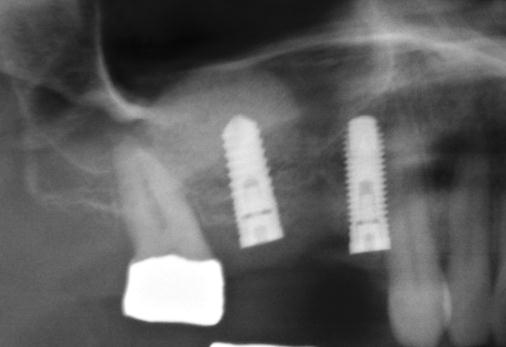

Nejčastější oblastí pro doplnění kosti je čeleni dutina horní čelisti.

Tento výkon se nazývá sinus lift - aplikace kostního granulátu do čelistní dutiny

Při ztrátě molárů a premolárů v horní čelisti a jejich náhradě implantáty se často setkáváme s nedostatečnou vertikální nabídkou kosti pod čelistní dutinou, často doprovázenou i nedostatečnou horizontální nabídkou a sníženou kvalitou kosti

(v oblasti 2. premoláru v 50%, v oblasti moláru až v 80% případů nedostatečná kostní nabídka)

Od roku 1985 je tento problém řešen augmentační operací nazývanou sinus lift.

Jedná se o vyzvednutí membrány, která čelistní dutinu vystýlá, pod vyzvednutou membránou vznikne kapsa, kam se umístí augmentační materiál, do kterého se zavedou implantáty.

Vhojení implantátů se při této operaci prodlužuje na 6-12 měsíců.